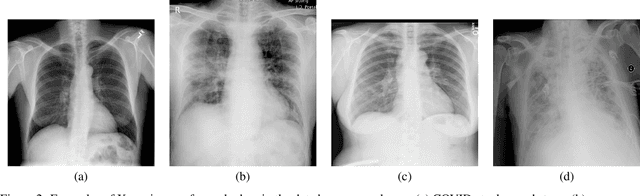

Abstract:Future SARS-CoV-2 virus outbreak COVID-XX might possibly occur during the next years. However the pathology in humans is so recent that many clinical aspects, like early detection of complications, side effects after recovery or early screening, are currently unknown. In spite of the number of cases of COVID-19, its rapid spread putting many sanitary systems in the edge of collapse has hindered proper collection and analysis of the data related to COVID-19 clinical aspects. We describe an interdisciplinary initiative that integrates clinical research, with image diagnostics and the use of new technologies such as artificial intelligence and radiomics with the aim of clarifying some of SARS-CoV-2 open questions. The whole initiative addresses 3 main points: 1) collection of standardize data including images, clinical data and analytics; 2) COVID-19 screening for its early diagnosis at primary care centers; 3) define radiomic signatures of COVID-19 evolution and associated pathologies for the early treatment of complications. In particular, in this paper we present a general overview of the project, the experimental design and first results of X-ray COVID-19 detection using a classic approach based on HoG and feature selection. Our experiments include a comparison to some recent methods for COVID-19 screening in X-Ray and an exploratory analysis of the feasibility of X-Ray COVID-19 screening. Results show that classic approaches can outperform deep-learning methods in this experimental setting, indicate the feasibility of early COVID-19 screening and that non-COVID infiltration is the group of patients most similar to COVID-19 in terms of radiological description of X-ray. Therefore, an efficient COVID-19 screening should be complemented with other clinical data to better discriminate these cases.